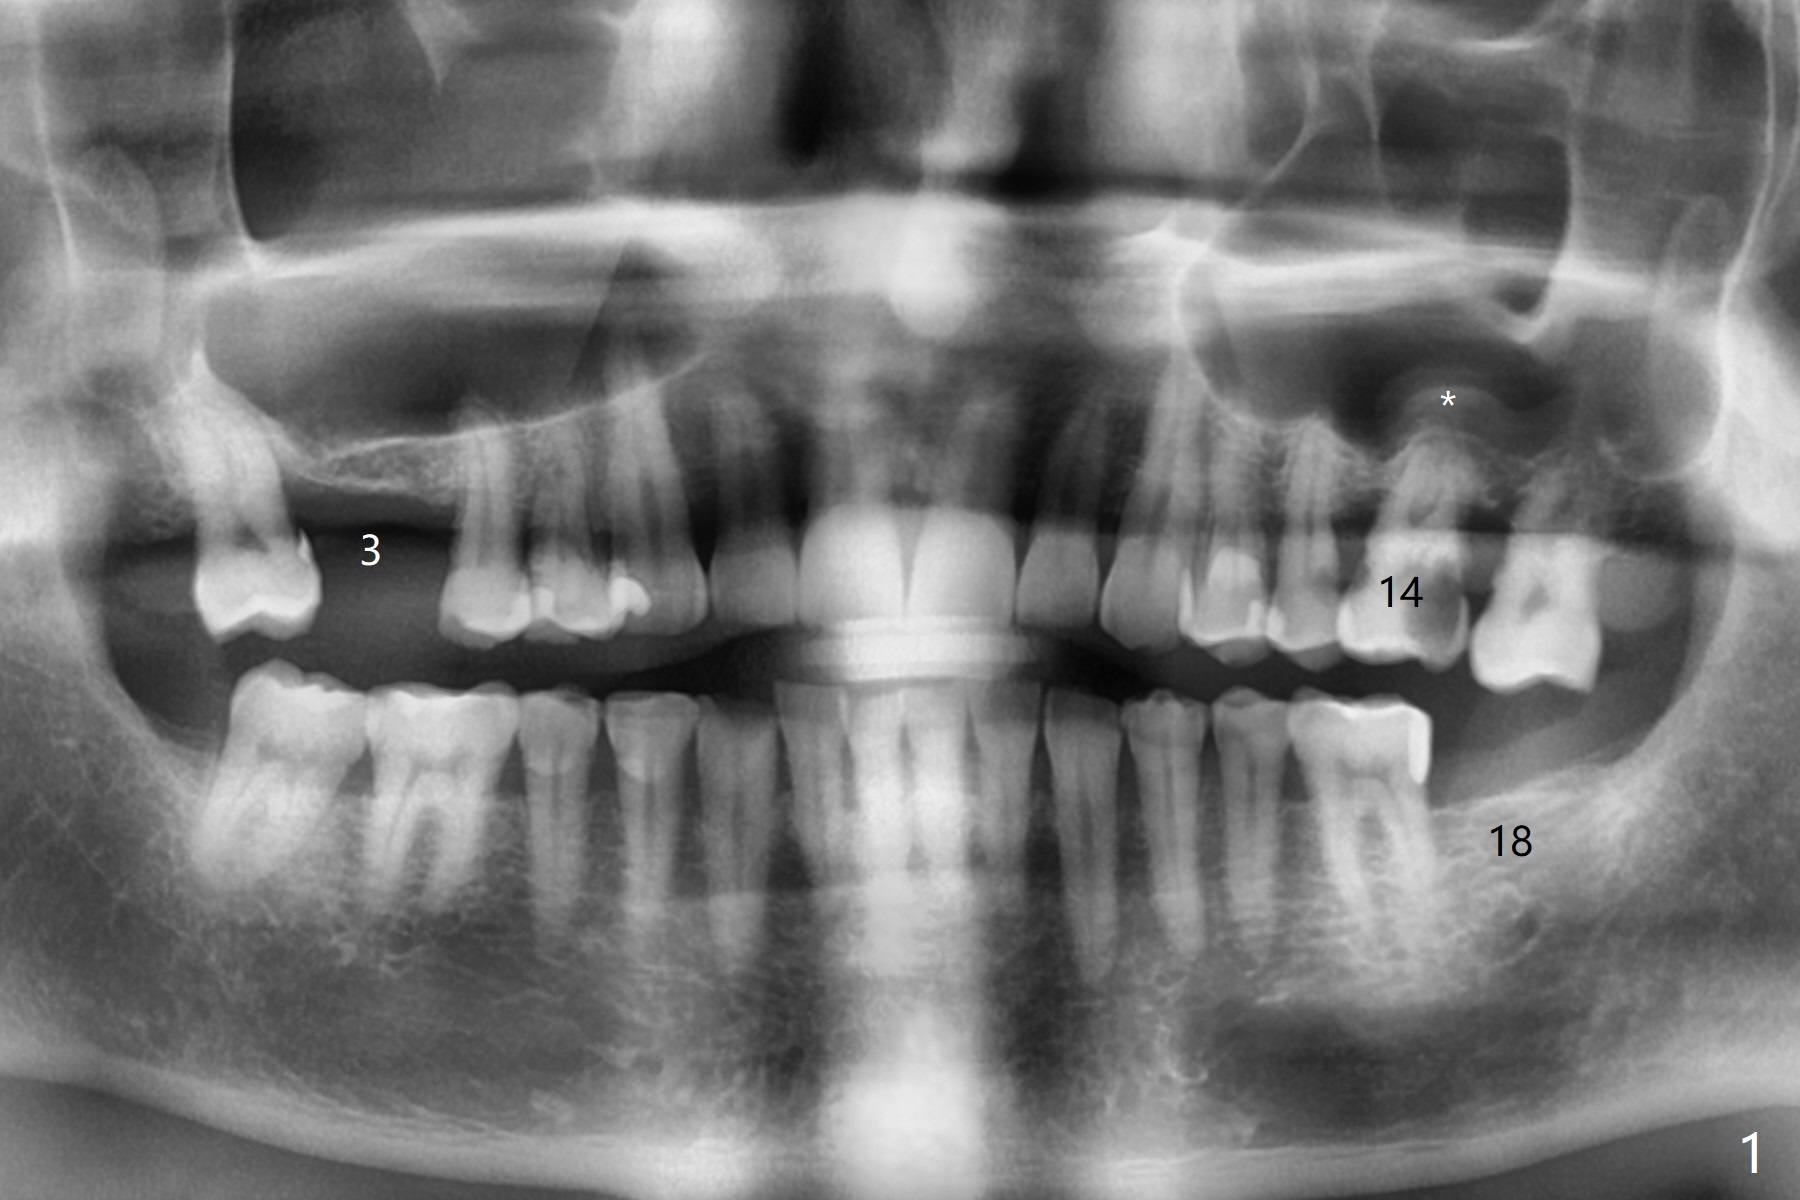

A 72-year-old man agrees to have #14 to be extracted for implant (Fig.1). In the first stage, impression is taken for #14 and 18 implant placement with guide. Due to odontogenic sinus infection (Fig.1,2 *), Z pack will be taken to prevent implant infection associated with sinus lift (Fig.2). Remove provisional and abutment once the sockets heal. To combat #15 supraeruption, the implant at #18 will be placed deep; if the torque is high, place a large diameter healing abutment or provisional with large base will be fabricated so that a short cuffed abutment will be used for final restoration. Heavy occlusal reduction at #15 will be conducted (Fig.3 curved lines). In spite of the fact that the bone height at #3 is 3-4 mm, the sinus floor is flat (Fig.4). Internal sinus lift is not expected to be too difficult. Use Magic Sinus Lifter, followed by implant placement at the same stage (Fig.5,6).